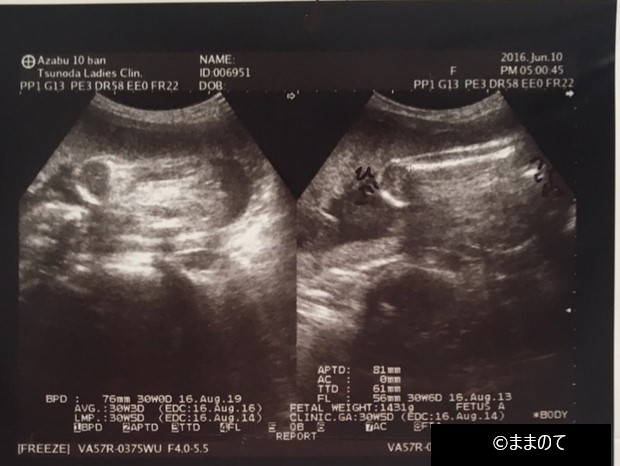

【女の子のエコー】妊娠30週

エコー写真の右上が足の付け根で、股間付近に突起物がないため、女の子だろうと判定されたときの写真です。妊娠30週になると、エコー写真に全身を写すのは難しくなります。さらに、画像がはっきりとしないことも多く、素人目ではなにが写っているか判断しづらいこともあります。

帰宅後に夫やきょうだいに写真の説明ができるよう、身体のどのあたりが写っているのか、医師に確認してみると良いかもしれません。